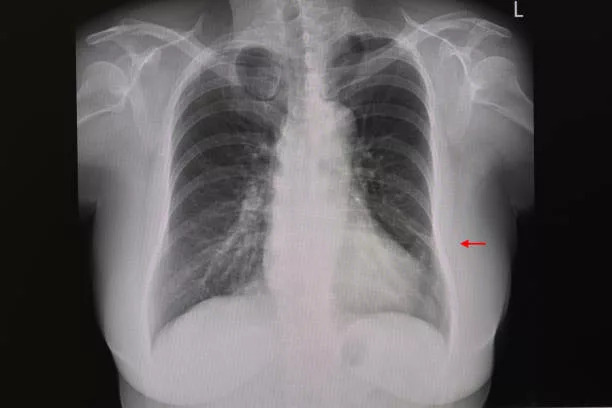

I went for a checkup and got an x-ray. Doc says that I might be having atelectasis but may need bronchoscopy for confirmation.

Another shows an x-ray which is quite similar to my case of Atelectasis

I have attached the image from there

I am already on supplemental oxygen when the breathing gets worse and by comparing my x-ray with those available online, I think my case isn't that bad.